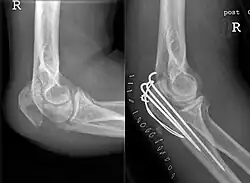

Eine Olekranonfraktur ist ein Bruch des Olecranon, das heißt der Oberkante der Elle am Unterarm, dort wo die Sehne des Armstreckers (Musculus triceps brachii) ansetzt.

Die Therapie muss meist operativ durch einfache Zuggurtungsosteosynthese erfolgen, bei Trümmerfraktur ist Plattenosteosynthese notwendig. Nach mindestens acht Wochen kann das Metall wieder entfernt werden.[1] Nur bei nicht verschobener Fraktur braucht bei Kindern nicht operiert zu werden.